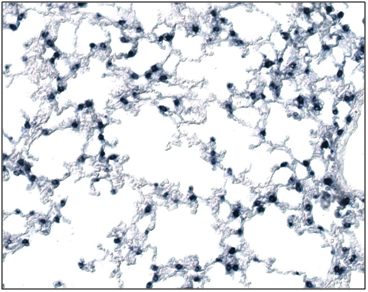

In order to investigate the distribution of FREAC-1 expression during organogenesis the Foxf1 Probe and the highest Foxf1 expression level is seen in the developing lung and evident already at 13dpi (Figure 1).

Figure 1 In situ hybridization analysis of Foxf1 expression in mouse lungs. In 13-dpi (A) Foxf1 expression is observed in mesenchymal cells especially in the cytoplasm.